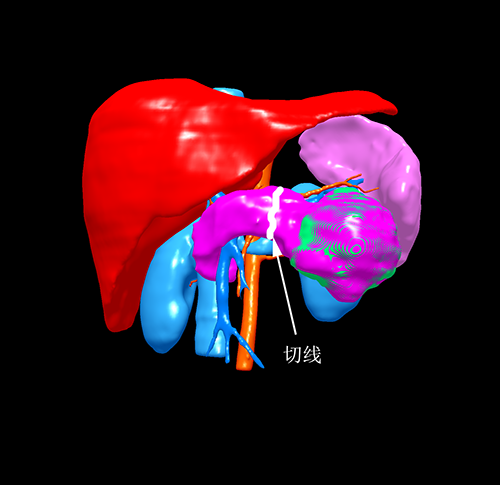

胰体尾实性假乳头状瘤---腹腔镜胰体脾切除